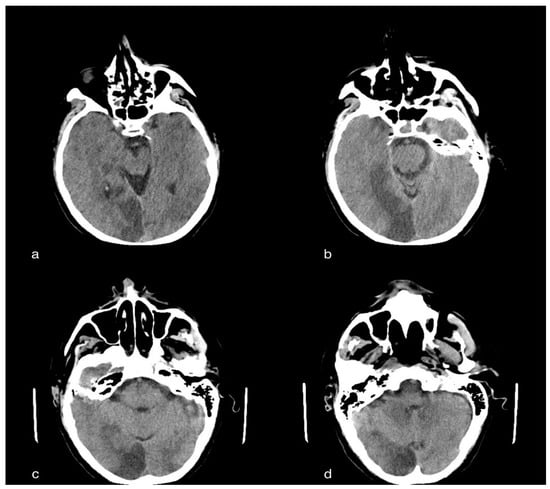

3.2.2. CT Imaging Findings

In the cerebral CT examination, we observed acute ischemic vascular pathology in the left temporoparietal region, with the cortico-subcortical site, extending to the ipsilateral deep white matter characterized by a small parenchymal hypodensity, and responsible for modest compression on the ipsilateral ventricular, subarachnoid and parenchymal compartments of the same side, but in the absence of deviation of the pellucid septum or third ventricle to the right of the midline or signs of intracranial hypertension (Figure 2).

Figure 2. A 60-year-old male patient with acute ischemic vascular pathology in the left temporo-parietal region, cortico-subcortical in origin, extending to the ipsilateral deep white matter, characterized by a slight parenchymal hypodensity, and responsible for the modest compression of the ipsilateral ventricular, subarachnoid and parenchymal compartment, but without deviation of the septum pellucid or third ventricle to the right of the line, subarachnoid and parenchymal compartments, but in the absence of deviation of the septum pellucid or third ventricle to the right of the median line or median line or signs of intracranial hypertension.